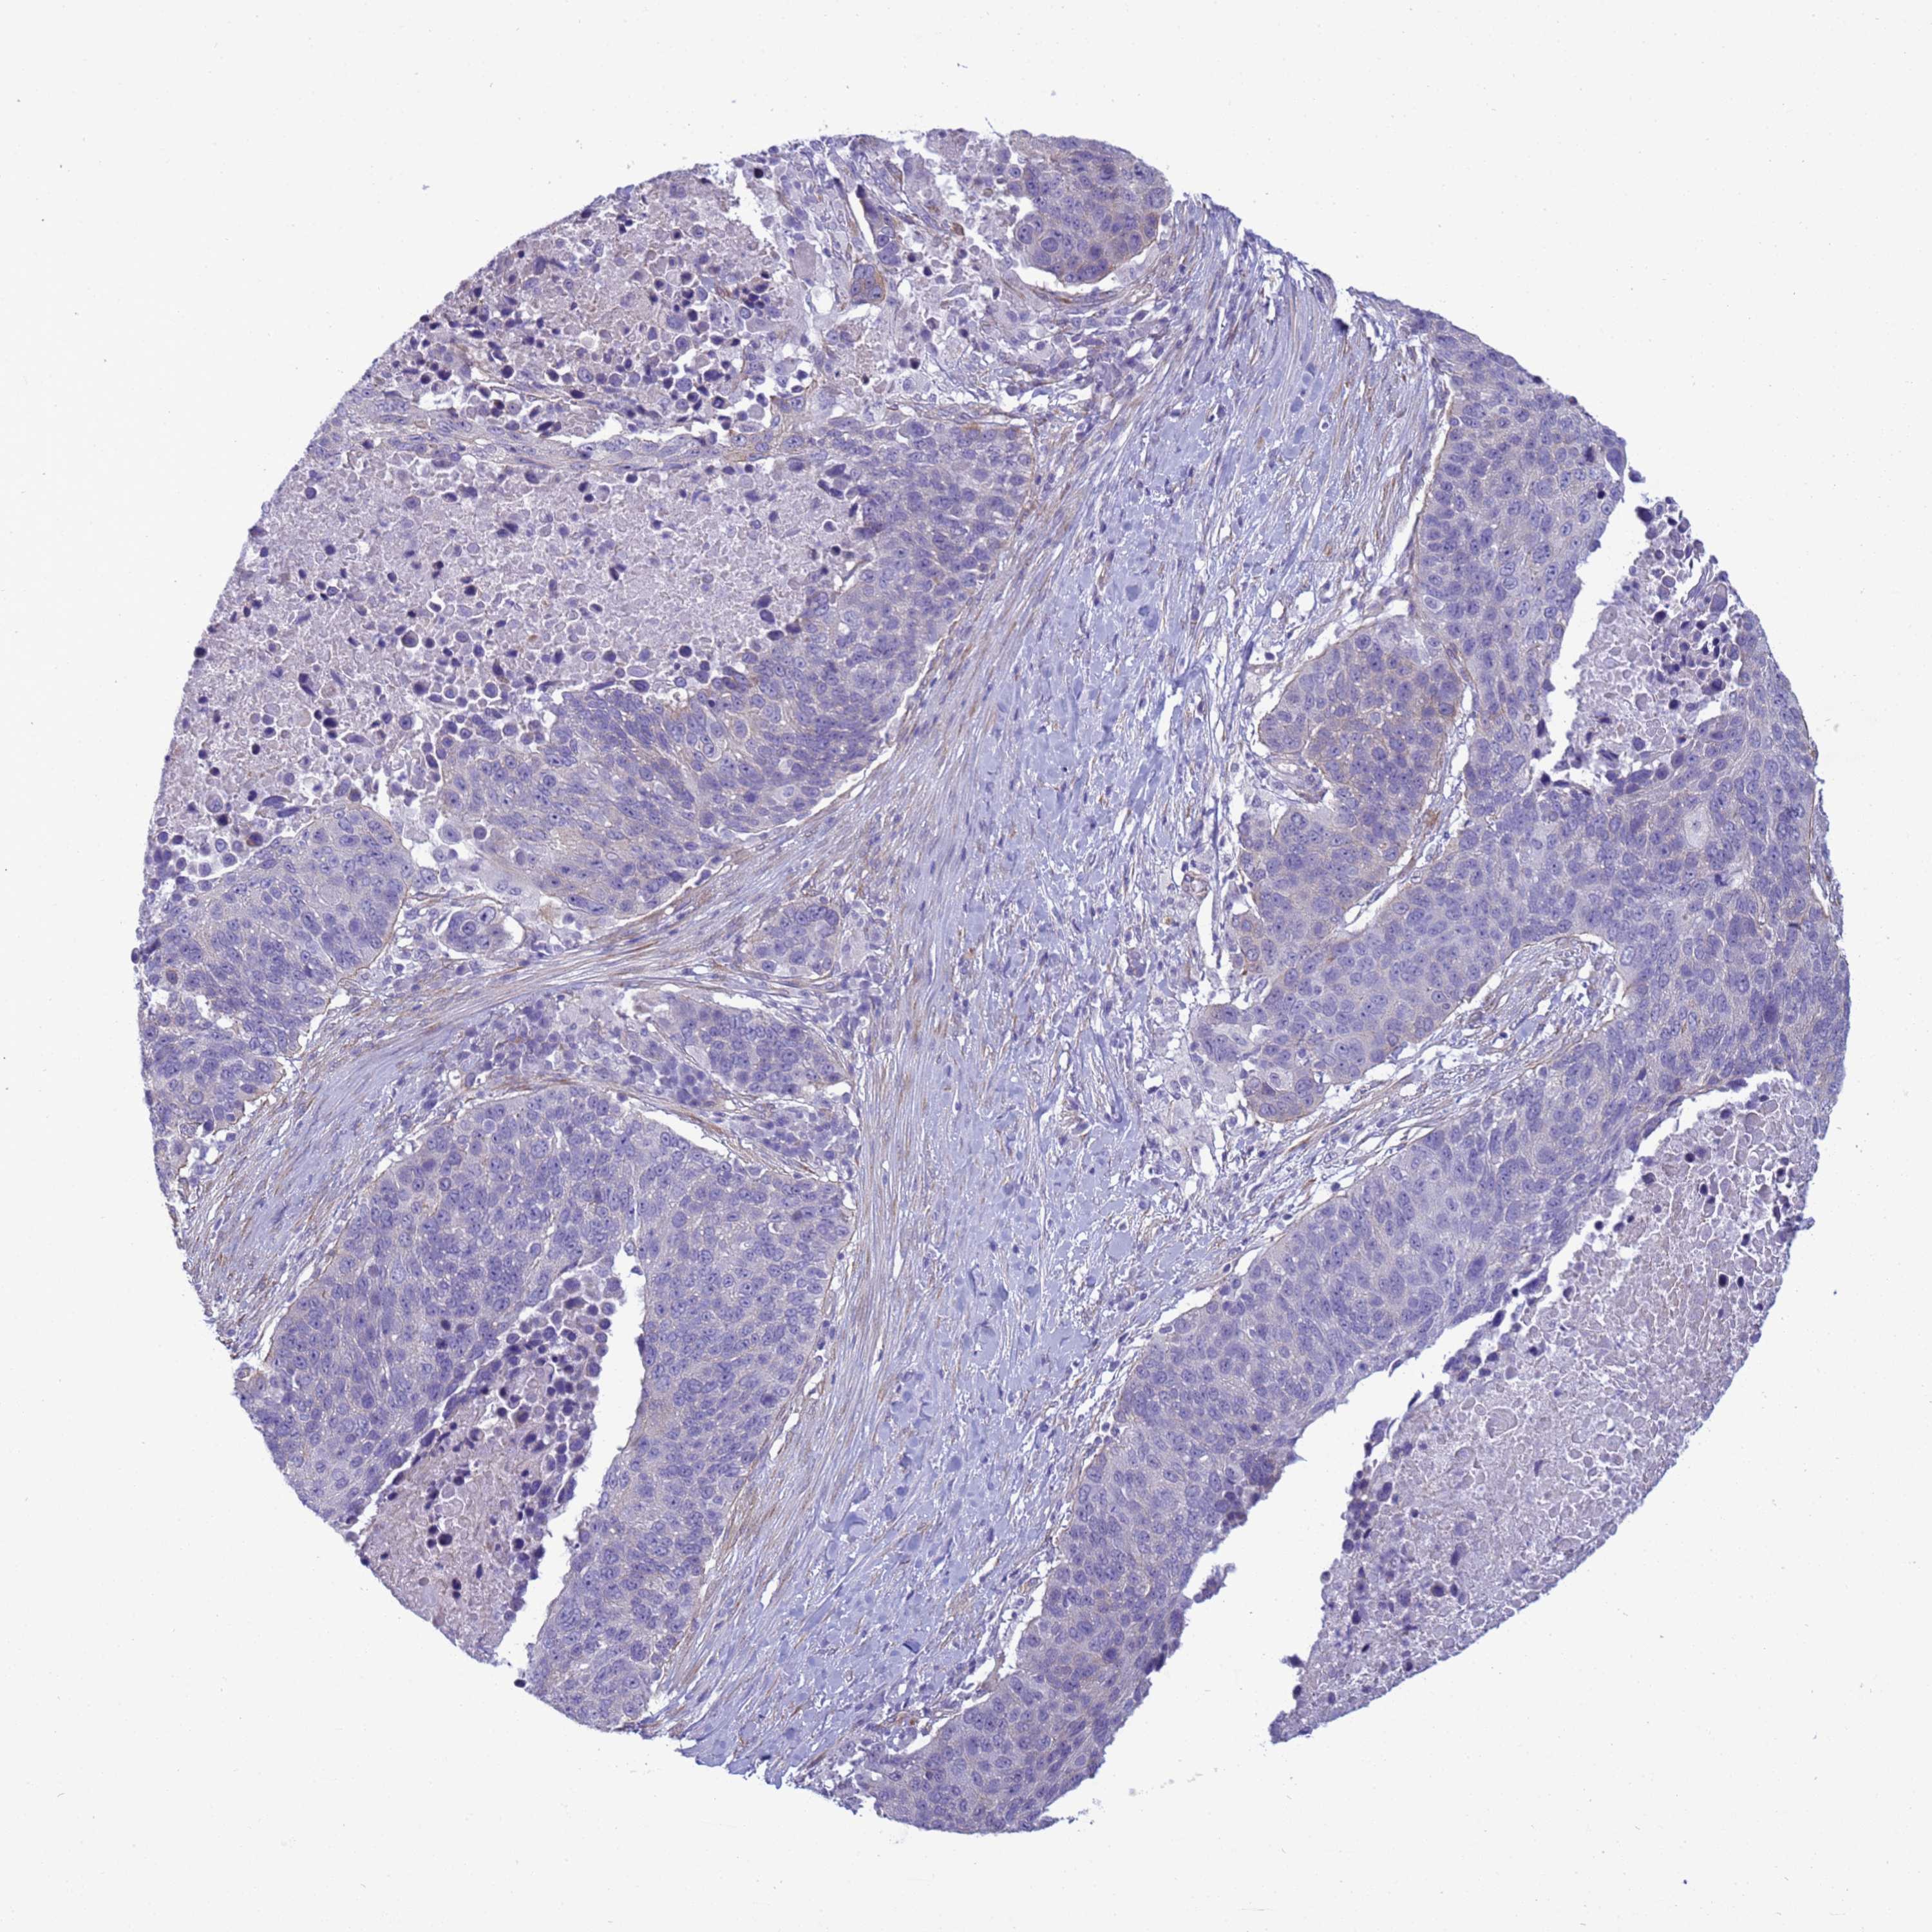

LUNG SQUAMOUS CELL CARCINOMA (TCGA) - Interactive survival scatter ploti

The Survival Scatter plot shows the clinical status (i.e. dead or alive) for all individuals in the patient cohort, based on the same data that underlies the corresponding Kaplan-Meier plots. Patients that are alive at last time for follow-up are shown in blue and patients who have died during the study are shown in red.

The x-axis shows the expression levels (FPKM) of the investigated gene in the tumor tissue at the time of diagnosis. The y-axis shows the follow-up time after diagnosis (years). Both axes are complimented with kernel density curves demonstrating the data density over the axes. The top density plot shows the expression levels (FPKM) distribution among dead (red) and alive patients (blue). The right density plot shows the data density of the survived years of dead patients with high and low expression levels respectively, stratified using the cutoff indicated by the vertical dashed line through the Survival Scatter plot. This cutoff is automatically defined based on the FPKM cutoff that minimizes the p-score. The cutoff can be changed by dragging the vertical line or by entering a cutoff value in the square labeled "Current cut-off".

Under the Survival Scatter plot the p-score landscape (black curve; left axis) is shown together with dead median separation (red curve; right axis). Dead median separation is the difference in median mRNA expression between patients who have died with high and low expression, respectively. It is calculated as follows: median FPKM expression of dead patients with high expression - median FPKM expression of dead patients with low expression. This is intended to aid the user in visually exploring custom cutoffs and the associated p-scores and dead median separation.

Individual patient data is displayed and can be filtered by clicking on one or more of the category buttons on the top of the page. Categories describing expression level and patient information include: high, low, alive, dead, female, male and tumor stages. The scale of the x-axis can be toggled between linear and log-scale by clicking on the "x log" button. Mouse-over function shows TCGA ID, patient information and mRNA expression (FPKM) for each patient.

& Survival analysisi

Kaplan-Meier plots summarize results from analysis of correlation between mRNA expression level and patient survival. Patients were divided based on level of expression into one of the two groups "low" (under cut off) or "high" (over cut off). X-axis shows time for survival (years) and y-axis shows the probability of survival, where 1.0 corresponds to 100 percent.

ITGB4 is not prognostic in Lung Squamous Cell Carcinoma (TCGA)

Best expression cut offi

: 100.35

P scorei

N/A

TCGA RNA samplesi

RNA-seq data is reported as average FPKM (number Fragments Per Kilobase of exon per Million reads), generated by the The Cancer Genome Atlas (TCGA) .

Normal distribution across the dataset is visualized with box plots, shown as median and 25th and 75th percentiles. Points are displayed as outliers if they are above or below 1.5 times the interquartile range. FPKM values of the individual samples are presented next to the box plot.

Average pTPM 223.3

Number of samples 489